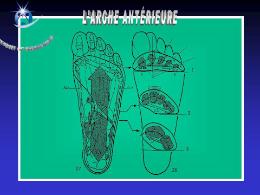

Anatomie du pied

Le squelette du pied est composé de 28 os qui se combinent en de nombreuses articulations.

Architecture d’un avant pied normal

La phalange du gros orteil et le premier métatarsien sont pratiquement dans le même alignement.